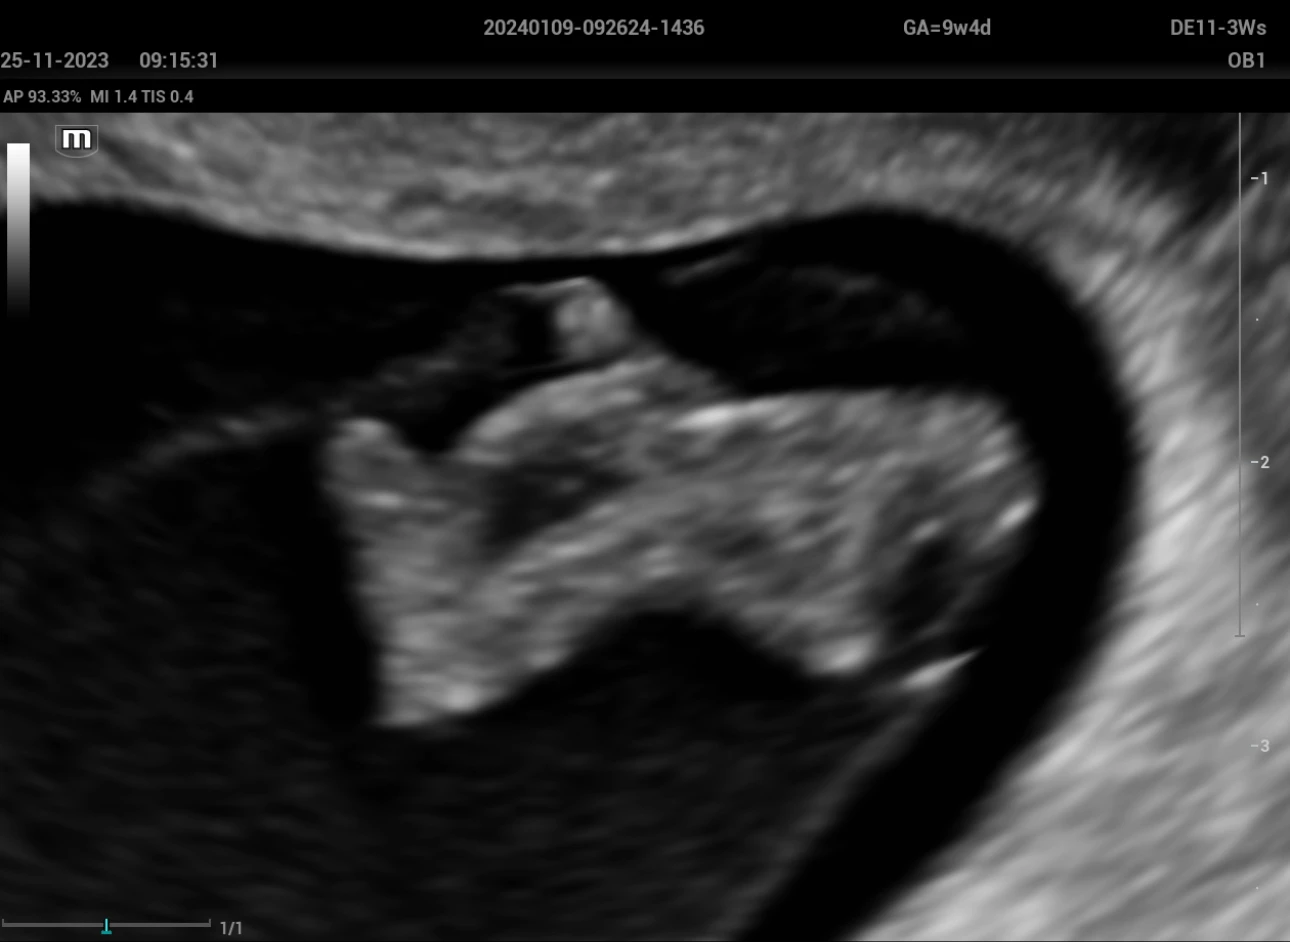

A woman of 22 years old, first pregnancy, marital status domestic partner, level education secondary schooling. The medical history includes a laparoscopic cholecystectomy 3 years ago and the first sexual relationship at the age of 15. The patient went to the Fetal Medicine Service of the Perinatal Maternal National Institute with a private ultrasound exam in which they consider a 9-week gestation + pleural effusion, so she was scheduled for a transvaginal ultrasound, which was performed with an Ultrasound System, model Nuewa I9 (Mindray) with an endocavitary volume transducer DE11-3Ws, observing a 26 mm CRL embryo, with cardiac activity of 171 B.P.M. who presents anencephaly (Figure 1), omphalocele (Figure 2), ectopia cordis (figure 3), hydrothorax and scoliosis (figure 4); Therefore, Body stalk is diagnosed, suggesting the interruption of the pregnancy as there is no prognosis for extrauterine life.

Omphalocele

Figure 2: Omphalocele